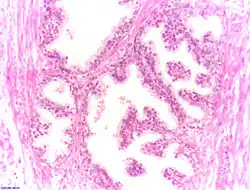

Adénocarcinome prostatique

Adénocarcinome prostatique- Adénocarcinome ; tissus indifférenciés

- Invasion périneurale par un adénocarcinome prostatique. HE, x400

Score de Gleason

La structure tissulaire des cancers de la prostate varie des formes différenciées (cellules cancéreuses ressemblant aux cellules saines), dite de grade 1, aux formes les moins différenciées (cellules cancéreuses présentant beaucoup de caractères atypiques par rapport aux cellules saines), dite de grade 5.

Plusieurs grades peuvent se rencontrer au sein d'un même tissu. Le score de Gleason est calculé de la façon suivante : on additionne les deux grades les plus représentés de la tumeur. Le premier chiffre représentant le score du contingent le plus représenté. Ainsi 4+3 est plus péjoratif que 3+4

Si la somme est de 6 ou moins, le cancer est dit bien différencié, donc de meilleur pronostic ; 7 : le cancer est moyennement différencié ; 8 ou plus : le cancer est peu différencié, donc de moins bon pronostic.